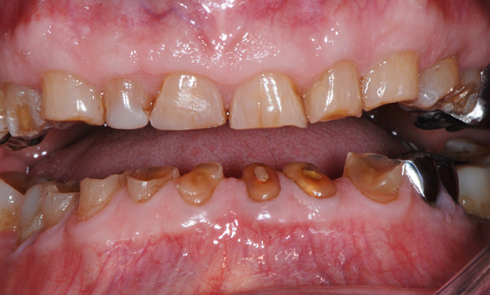

Article réservé à nos abonnés Réhabilitation d’un patient “gueule cassée”

Nous nous proposons de décrire la restauration d’un cas clinique particulier, victime d’un traumatisme dento-maxillo-facial important. Nous insisterons sur l’aspect...